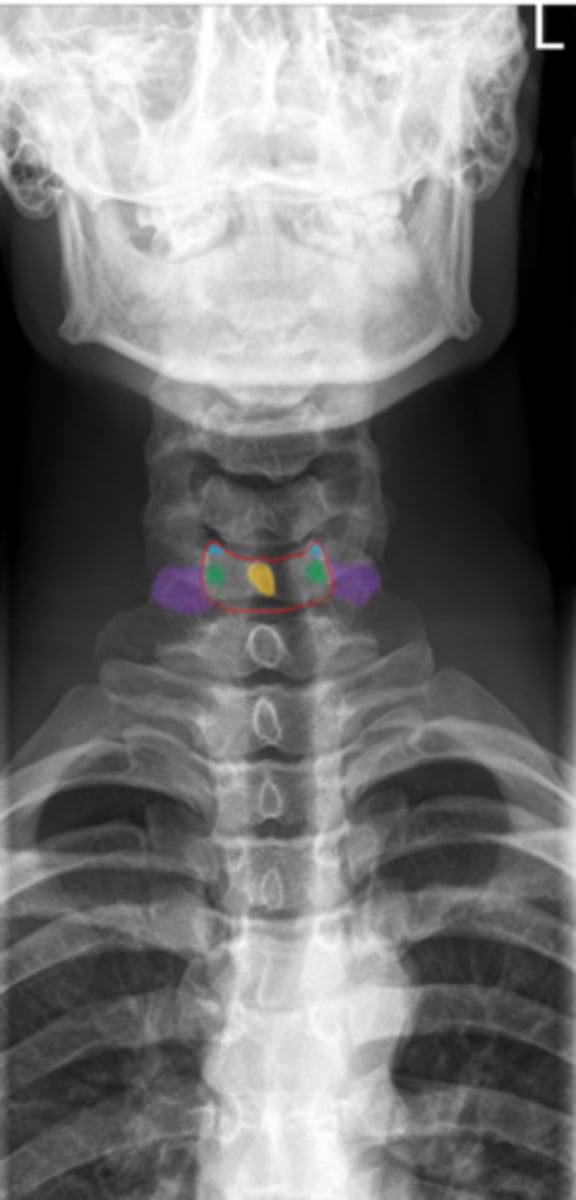

C1 and C2

What vertebrae is being examined?

Odontoid process (dens)

Identify the purple structure

anterior arch/tubercle

Identify the red structure

posterior arch/tubercle

Identify the green structure

lateral masses

Identify the blue structure